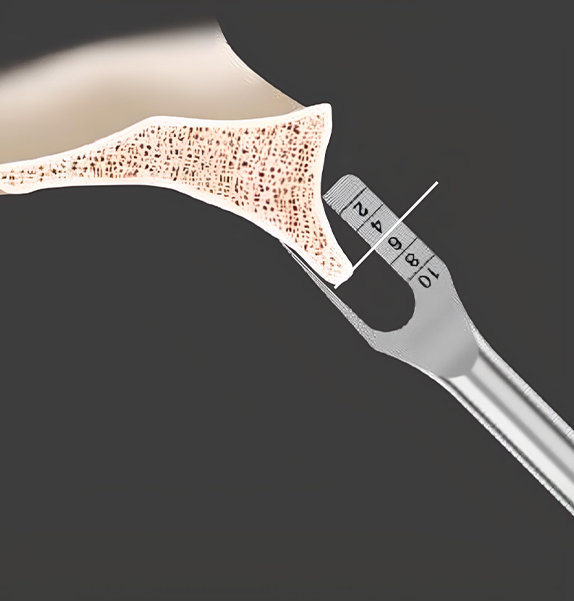

Basal Bone Zone에 위치한 KnifeThread®가 식립 즉시 더 높은 ISQ Value를 보장합니다.

MegaGen의 특별한 Deep & KnifeThread® 디자인 적용으로 기저골에서도 역시 식립 즉시 높은 초기 고정력을 확보합니다. 또한 압축력(Compressive Force)에 대한 저항력을 높이는 동시에 전단력(Shear Force)의 발생을 최소화 합니다.